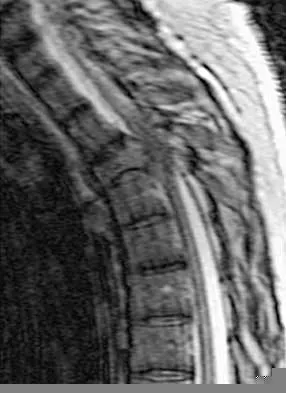

Question 16

Figures 3a and 3b show the MRI scans of a patient with neck pain. What is the most likely diagnosis?

Explanation